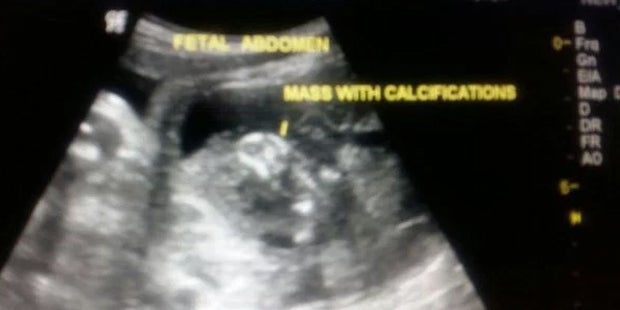

Da staunten die Eltern im indischen Mumbai nicht schlecht. Eine 19-jährige Frau brachte einen eigentlich gesunden Buben zur Welt. Im Magen des Neugeborenen fanden die Ärzte dann aber etwas Unglaubliches: Der Bub war „schwanger“ mit seinem Zwillingsbruder.

Der halb-formierte Körper des Zwillings wies Arme, Beine und sogar ein Gehirn auf. Wie der Express und andere Medien berichten, war die Masse des Fötus rund sieben Zentimeter groß. Die Ärzte konnten den Fötus schließlich erfolgreich operativ entfernen, Mutter und Bub sind wohlauf.

Unter foetus in foeto versteht man ein sehr seltenes medizinisches Phänomen, bei dem sich zunächst zwei oder mehr Föten im Mutterleib entwickeln und danach ein Fötus oder mehrere Föten in den anderen einverleibt werden. Weltweit sind weniger als hundert derartige Fälle einer fetalen Inklusion bekannt.